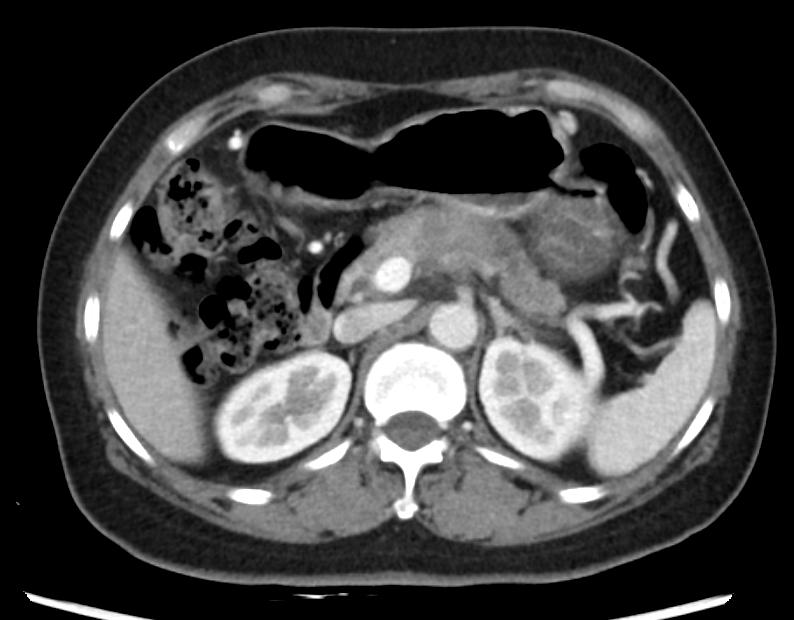

入院以后还需要进一步了解肿瘤的大小、部位、是否有侵犯到其他器官等,完善了腹部增强CT、胸部CT和超声胃镜等检查。CT胸部平扫(2019-08-16 13:21):左肺微小结节,左肺纤维灶。CT上腹部平扫+增强(2019-08-20 16:39):胰腺颈体部胰腺癌伴脾动脉受侵考虑,脾静脉可疑受侵。 腹膜后多发稍肿大淋巴结。MR(磁共振)上腹部平扫+增强+MRCP(2019-08-17 15:49):胰腺颈体部占位(考虑胰腺癌),病变侵犯脾血管、腹腔干分叉部;腹膜后多发稍肿大淋巴结。ES(内镜)超声胃镜(2019-08-21 15:20):胰颈低回声病灶。

2019-8-20上腹部增强CT